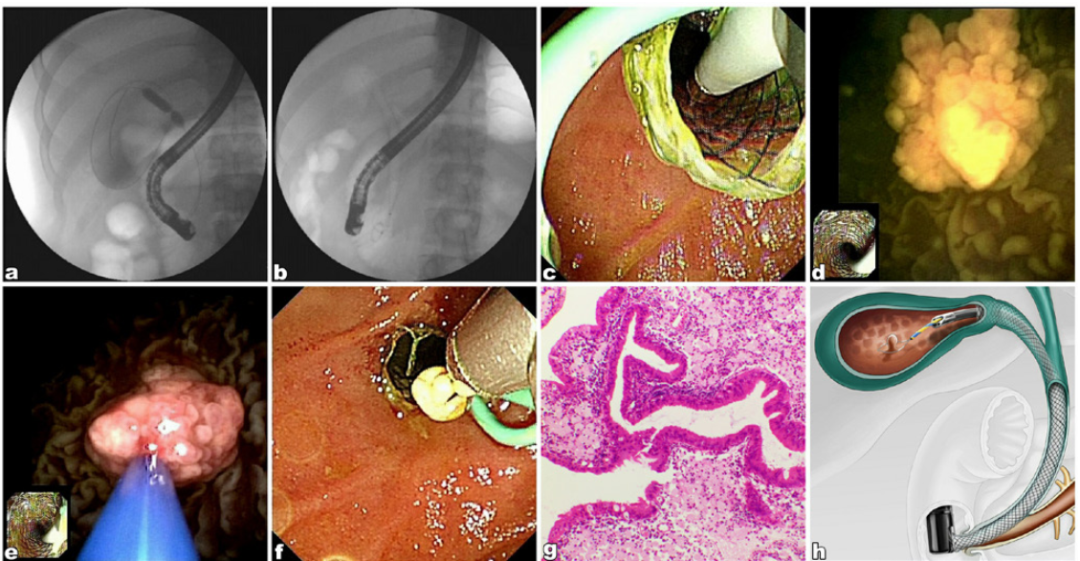

胆胰管镜实现胆胰微小病变诊治一体化

对于胆胰管内≤1.5 cm的息肉、乳头状瘤等微小病变,传统方案存在“过度手术”或“被动随访”的困境。来自我国4中心前瞻性队列研究证实单人操作胆胰管镜(SOC)引导下内镜黏膜切除术(EMR)可实现“超级微创”治疗。该研究纳入20例胆胰系统病变患者(13例胆囊病变、5例胆管病变、2例胰管病变),采用胆胰镜辅助内镜黏膜切除术(CA-EMR)进行治疗,技术成功率达100% ,整块切除达85.0%,平均手术时间为48.9 min,仅2例出现轻微不良事件(轻度术后胰腺炎、胆管炎),经保守治疗痊愈,中位随访时间为12.5个月且无复发。证实该技术对≤1.5 cm的胆胰管内病变具有可行性和安全性,为避免手术过度治疗提供了新选择。